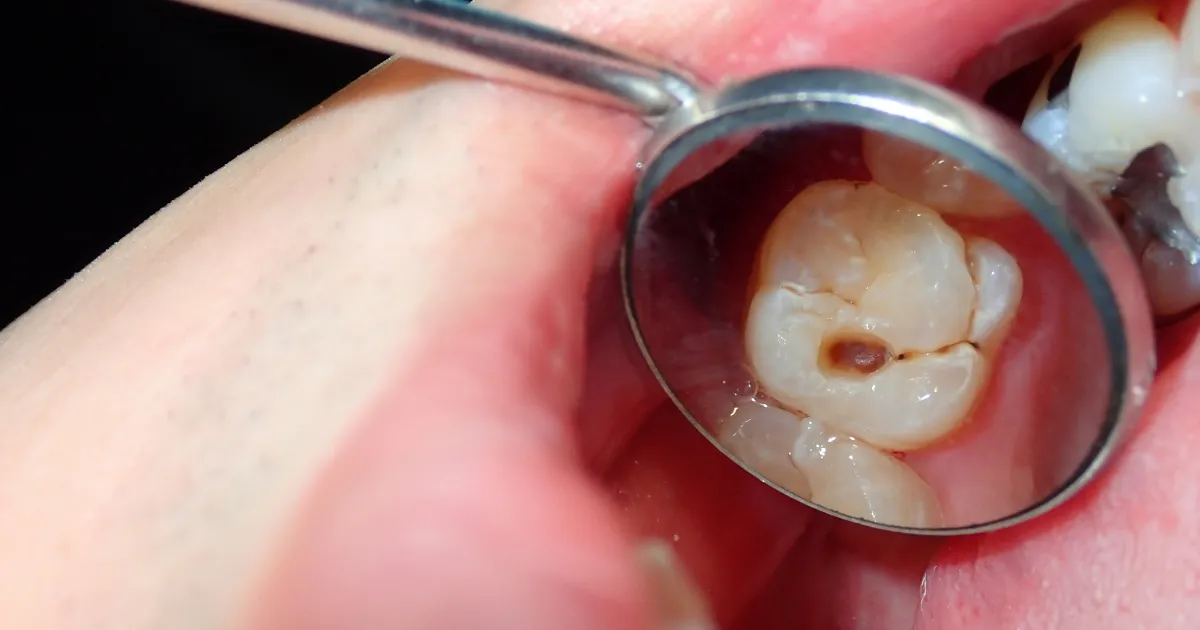

検査・診察

口腔内診査はもちろんのこと、X線撮影やCTスキャンを用いて、親知らずの位置や状態を詳細に調べます。

これにより抜歯が必要かどうか、またその難易度を判断します。